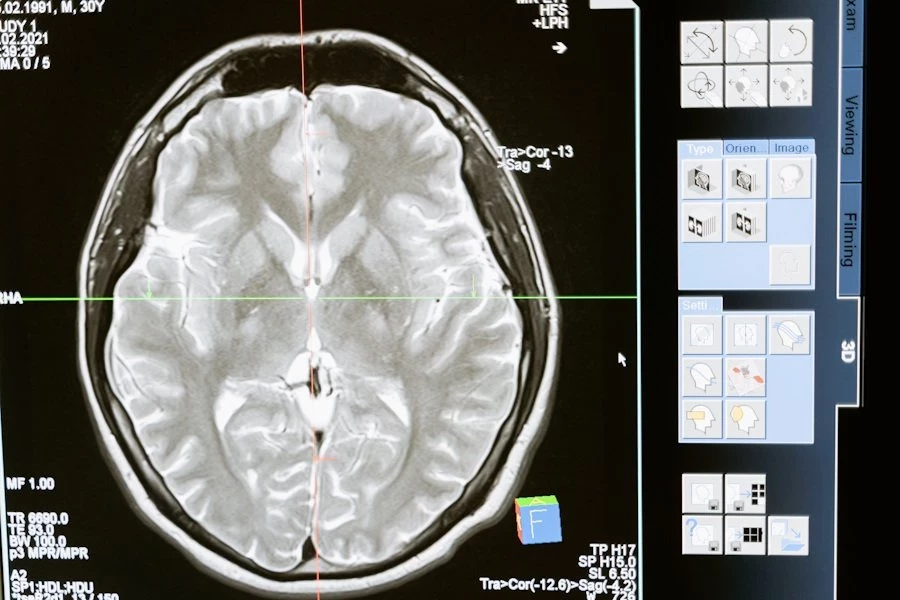

Учёными National Institute on Aging (США) проведено исследование для выявления связей определенных белков с возникновением деменции — состояния, при котором ухудшаются память и поражается мозга человека. Исследование может стать базой для разработки новых методов диагностики и лечения заболеваний, вызывающих деменцию. Доклад о работе обнародован на портале Science Translational Medicine.

Ученые выявили 32 белка, регуляция которых в возрасте от 45 до 60 лет была сильно связана с возможностью развития деменции в пожилом возрасте. Некоторые из этих белков играют важную роль в мозге, но большинство выполняют другие функции в организме.

Особый интерес вызвали белки, связанные с процессом протеостаза — это контролирующий механизм, который балансирует уровень белков в организме. Этот механизм важен для предотвращения скопления белков в мозге, что часто наблюдается у людей с болезнью Альцгеймера, наиболее распространенным видом деменции.